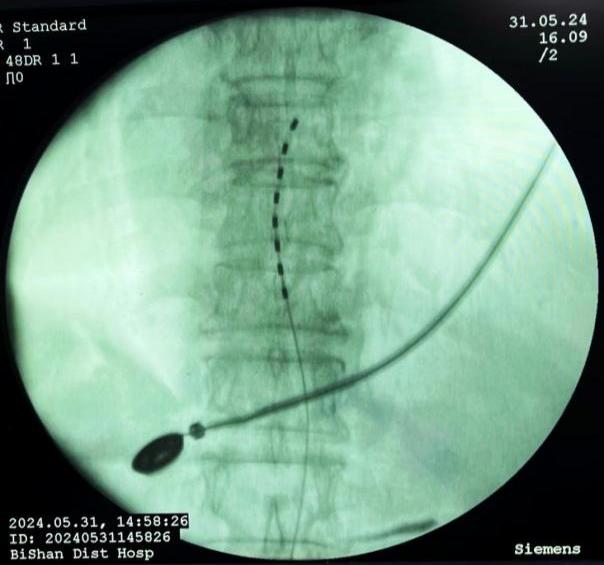

3.癌痛規范化管理:癌痛是癌癥患者最常見和難以忍受的癥狀之一,不僅嚴重影響患者的睡眠、飲食,而且加重患者心理負擔,導致焦慮、抑郁等,嚴重影響患者的生活質量。癌痛的治療方法包括:病因治療、藥物止痛治療和非藥物治療。癌癥患者常面臨難以控制的疼痛,傳統的藥物治療在這些患者中可能效果有限或伴隨嚴重副作用??剖以阼瞪降貐^率先采用了鞘內藥物輸注(Intrathecal Drug Delivery, IDD)進行癌痛管理,通過將藥物直接輸送到脊髓鞘內,可以顯著提高藥物的局部濃度,從而增強鎮痛效果并減少全身副作用。

鞘內泵植入術